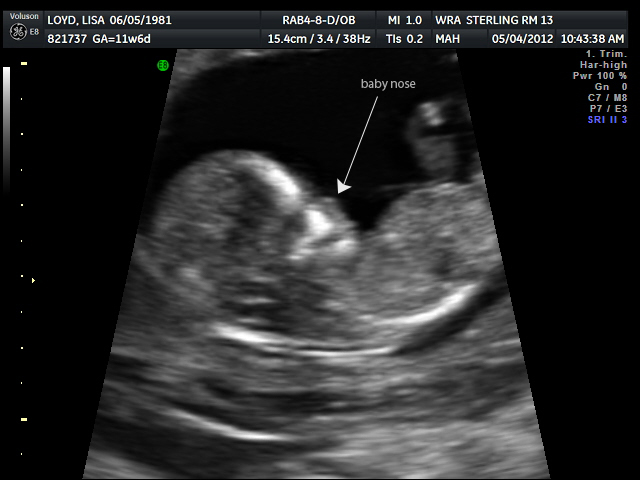

Once your mom and I got in to see the doctor I saw the most amazing thing I have ever seen in my life. There you were on the computer screen. Moving around. Waving. Covering your eyes. Shifting your legs.

Five little fingers on at least one hand could be seen and you became really real to me. It was something people have said over and over and I believe them now...you don't understand how much having a child means until it happens to you. Today...it happened to me.

The outcome was all positive and we even got to see some 3D images of you. To be honest, for as amazing as it is to see you, you look like an alien still. Hopefully you'll grow up to be much better looking :)